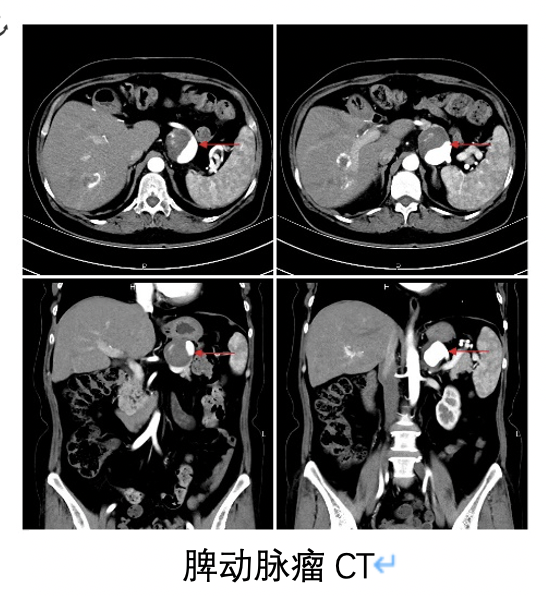

脾动脉瘤的检查

什么是脾动脉瘤?

脾动脉瘤介入治疗一例